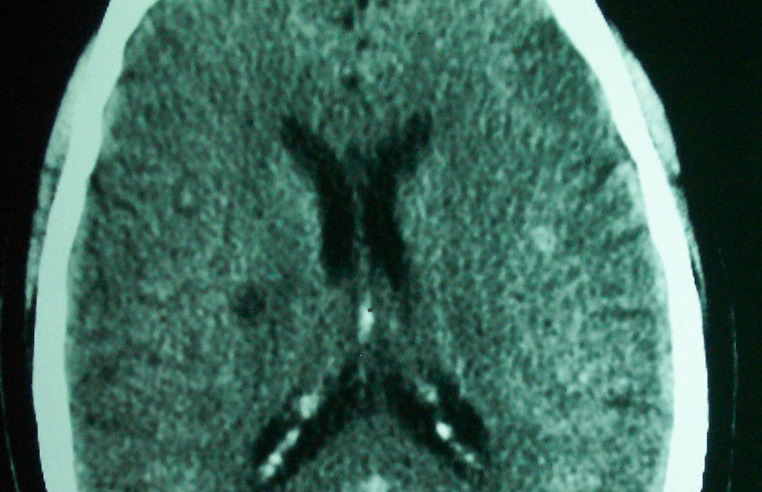

标题: CT18022:颅内多发稍高密度影

f     60    左侧肢体活动无力3天余,    神志情,  无抽搐史   无发热   否认囊虫接触史

有囊有节有钙化,这个表现符合混合型脑囊虫病.请结合临床资料并进行补体结合试验.

有囊有节有钙化,考虑混合型脑囊虫病.